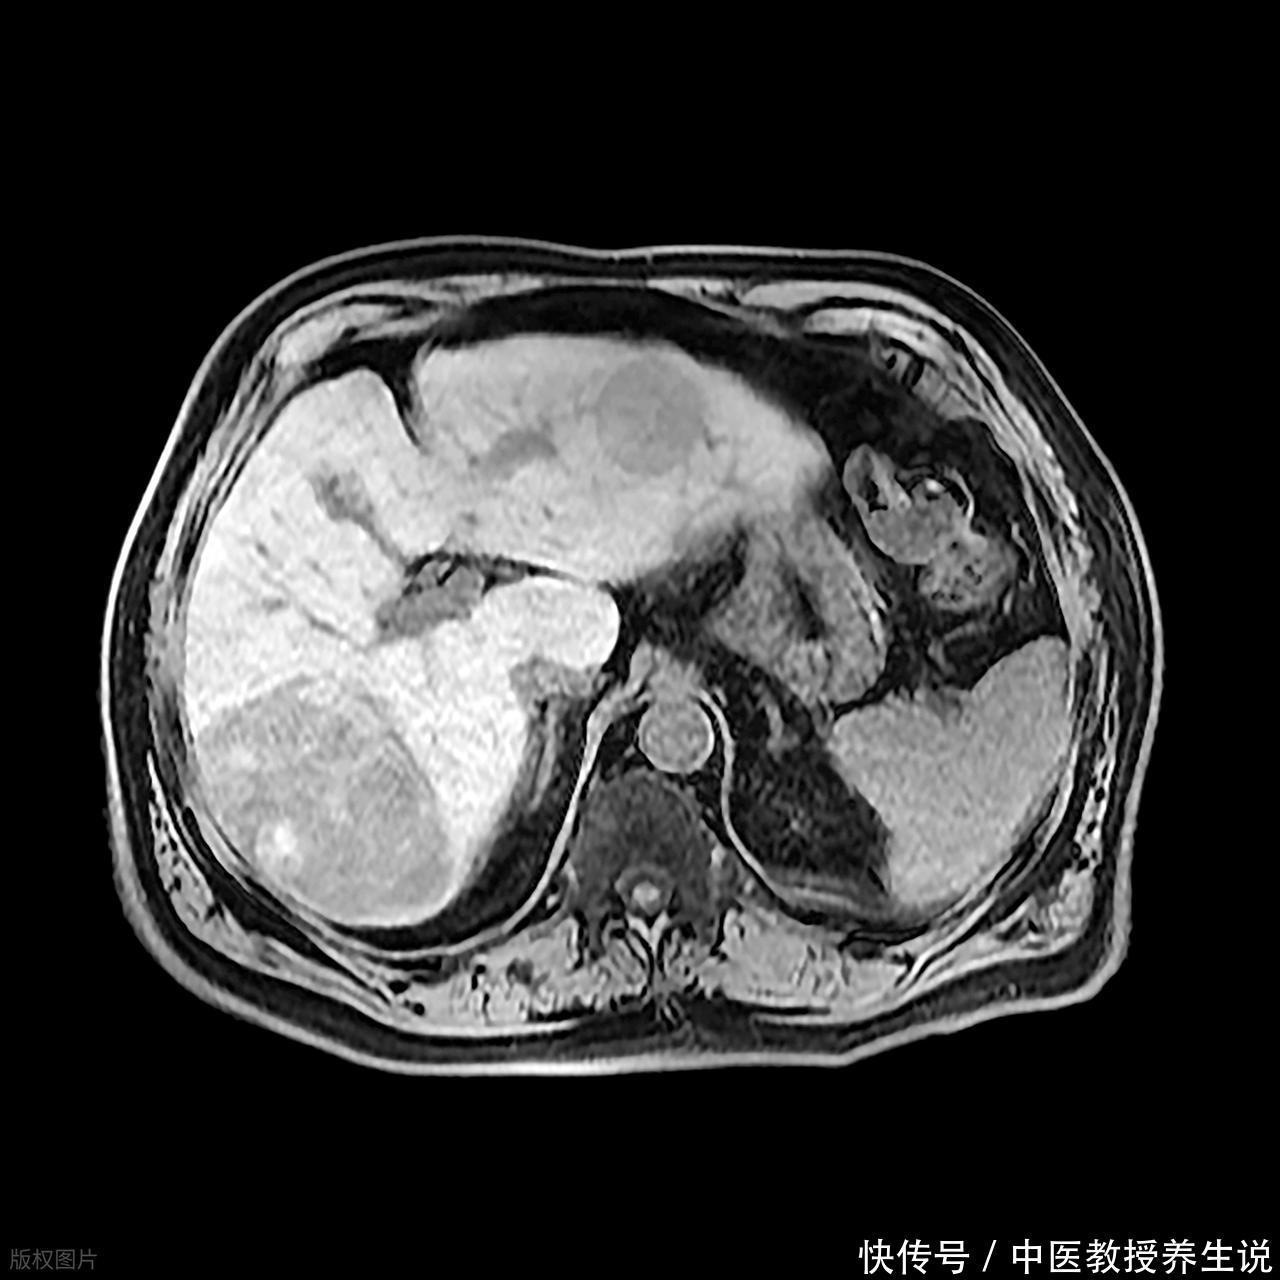

这事儿也不能一概而论,真到了肝脏那层被膜变得坑坑洼洼,或者是超声医生皱着眉头说“回声增粗、分布不均”的时候,那就别省那点钱了。有些微小的、只有几毫米的“小坏蛋”,尤其是那种长在肝脏边缘或者膈顶这种超声死角的,或者是已经有了肝硬化底子的肝脏,那是必须要上增强CT或者核磁共振来“照妖”的。

这时候普通的平扫就像是在雾里看花,非得往血管里打点药,利用癌细胞抢血抢得快、退得也快的特性,来个“快进快出”的对比,才能把那个坏东西给揪出来。当然,这也得结合那个叫甲胎蛋白的指标,要是这指标莫名其妙往上窜,哪怕片子上看着干净,也得往深了查,哪怕是那个不仅贵还费时间的核磁共振,该做也得做。